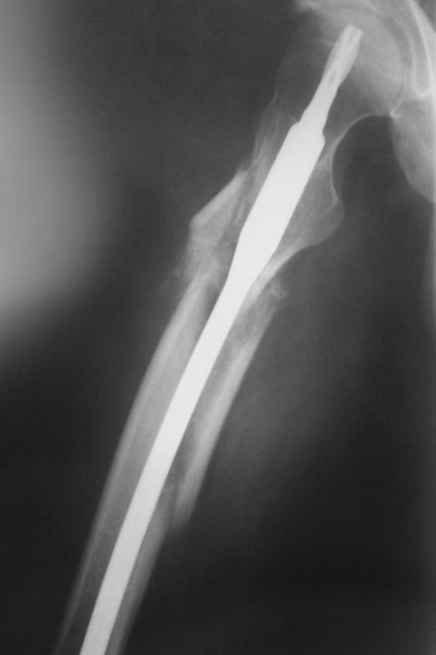

На операции я оставил осколок в области приводящих мышц бедра (ни пальпаторно, ни спицей сдвинуть не смог, "заклинило" насмерть). Фото спустя 2 месяца после операции (PFN).

Только сейчас пациент стал более или менее активным. Сразу после операции жалобы на сильные боли при отведении и приведении бедра в области отломка. Сейчас отломок пальпируется и пациент испытывает дискомфорт, хотя амплитуда движений объективно прогрессирует.

Теперь думаю, надо все-таки было через минидоступ или резецировать, либо репонировать. Обычно при таких операциях уже на 2-й день пациенты на костыли и по отделению, а у этого задержка длительная получилась. Только спустя 2 недели кое-как на костыли взобрался. Ни отека, никакой неврологии, только эти боли в области осколка.